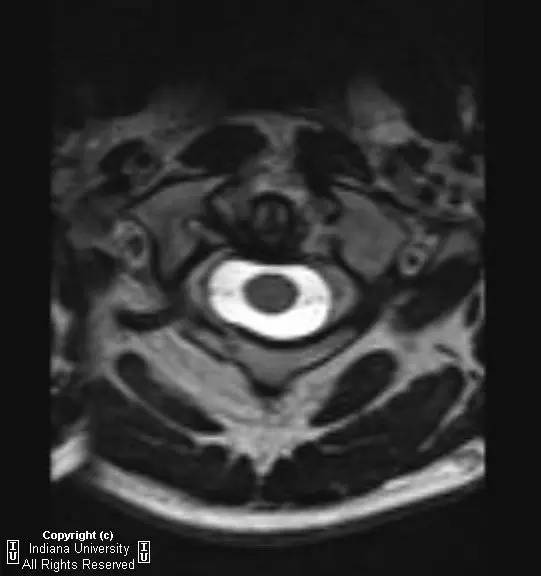

CR: C1侧块相对C2侧块外侧移位约5 – 6 mm,符合Jefferson骨折。椎体周围软组织明显肿胀。MR: 椎体周围间隙可见血肿。覆膜完整。寰枕前韧带断裂。寰枢前韧带完整。左侧横韧带从C1侧块的内侧分离,CT对应在C1侧块内侧见小撕脱骨折。翼状韧带完整。寰枕后韧带完整。前纵韧带和后纵韧带完整。黄韧带完整。

Jefferson骨折(Jefferson fracture)是前后弓均累及的C1环粉碎性骨折。Jefferson骨折为头顶受打击并轴向载荷的结果,力从颅骨经枕骨髁传递到颈椎,C1侧块在枕骨髁和C2上关节面之间被压缩,基于侧块的形状产生向心力而导致C1爆裂骨折。齿状突开口位或冠状位重建CT图像应仔细观察双侧C1和C2关节侧块间有无偏移。虽然C1侧块相对C2上关节面侧方移位提示存在骨折,但在X线片上有时难以发现骨折线。MR可显示相应的韧带损伤。

Jefferson骨折。A,侧位片示C1后弓骨折线(箭)。B,开口位示C1侧块相对于C2偏移(箭)。C和D,轴位CT图像示骨折线通过C1环前、后部(箭)。E,冠状位CT图像示翼状韧带小的撕脱骨折(黑箭)。此图像上也标注了C1在C2上方偏移(白箭)。